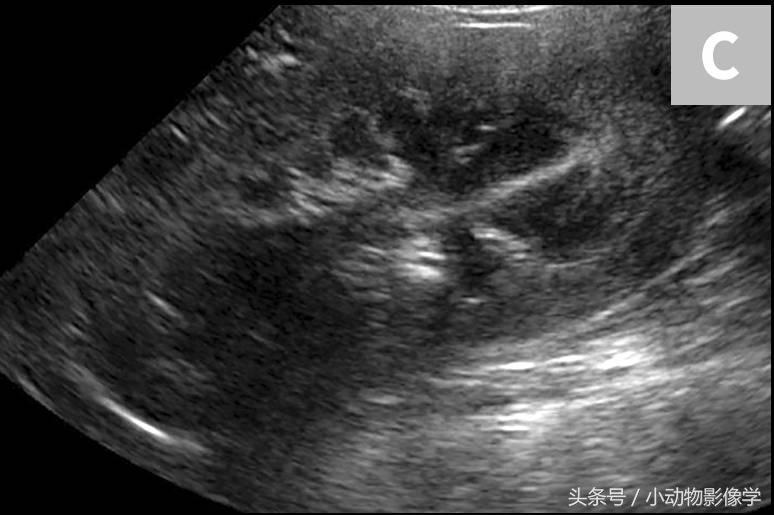

图1C、犬正常右肾的矢状面超声图像。相对于图1B,该图像同样取长轴方向,但是切口与背面相垂直。皮质和髓质看上去是一样的,但肾盂在图像深处中缺失(位于平面外)。